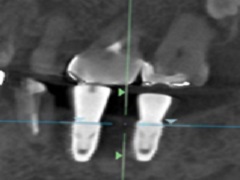

③ 装着

完成したサージカルプレートをインプラント手術前に口腔内に装着した状態でインプラント手術を開始します。

このことにより、計画した通りの位置で施術が可能となります。